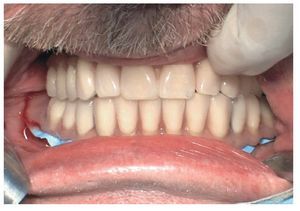

Pese a ello, es importante someter las estructuras a un control visual y mecánico, a fin de corregir eventuales discrepancias menores (figs. 99 a 102). A continuación se procede al montaje utilizando dientes protésicos prefabricados de composite (SR Phonares NHC, Ivoclar Vivadent, Ellwangen, Alemania), los cuales reproducen el tipo funcional correspondiente en virtud de sus propiedades morfológicas y estructurales y se integran armoniosamente en cuanto a su longitud dental (figs. 103 a 105). Durante la comprobación de las restauraciones protésicas, se evalúan clínica y radiológicamente ante todo la pasividad y la precisión del ajuste de la estructura. Acto seguido se lleva a cabo una comprobación de la oclusión y de la dimensión vertical, del estado de las prótesis y del tejido blando en la cresta alveolar, así como la verificación del espacio libre lingual, incluida la fonación, y el apoyo de los labios y las mejillas (figs. 106 y 107). También se debe comprobar la facilidad de higiene de la restauración de acuerdo con las habilidades manuales del paciente. A continuación se debe verificar la posición tridimensional de los dientes anteriores con los labios cerrados y durante la sonrisa, así como el aspecto global de la rehabilitación protésica.

Para la rehabilitación definitiva del paciente (figs. 116 a 124) deben comprobarse de nuevo todos los aspectos de la sesión anterior y debe procederse a la cementación de las prótesis. Son indispensables controles de seguimiento a corto plazo (al cabo de 1, 3 y 5 semanas) para el ajuste óptimo de la oclusión y la comprobación de la higiene oral con una prótesis que habitualmente ofrece aberturas de acceso periimplantares más estrechas que una prótesis provisional. Tres y seis meses después de la finalización del tratamiento se deben realizar controles clínicos, y una vez al año deberían llevarse a cabo sendos controles clínico y otro radiológico.

Figs. 116 y 117. Las restauraciones definitivas fijadas a los implantes. Cabe destacar la buena curación del tejido blando periimplantar.

Figs. 118 a 120. La situación intraoral final.